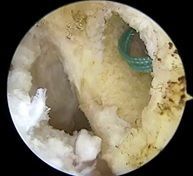

![]() | ![]() | ![]() |

| 大腿骨孔作成 | グラフト挿入 | 再建靱帯 |